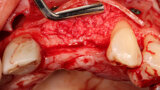

Fig. 3: A full thickness flap was created to expose the deficient facial aspect of the edentulous premaxilla that will receive augmentation to accommodate implant placement.